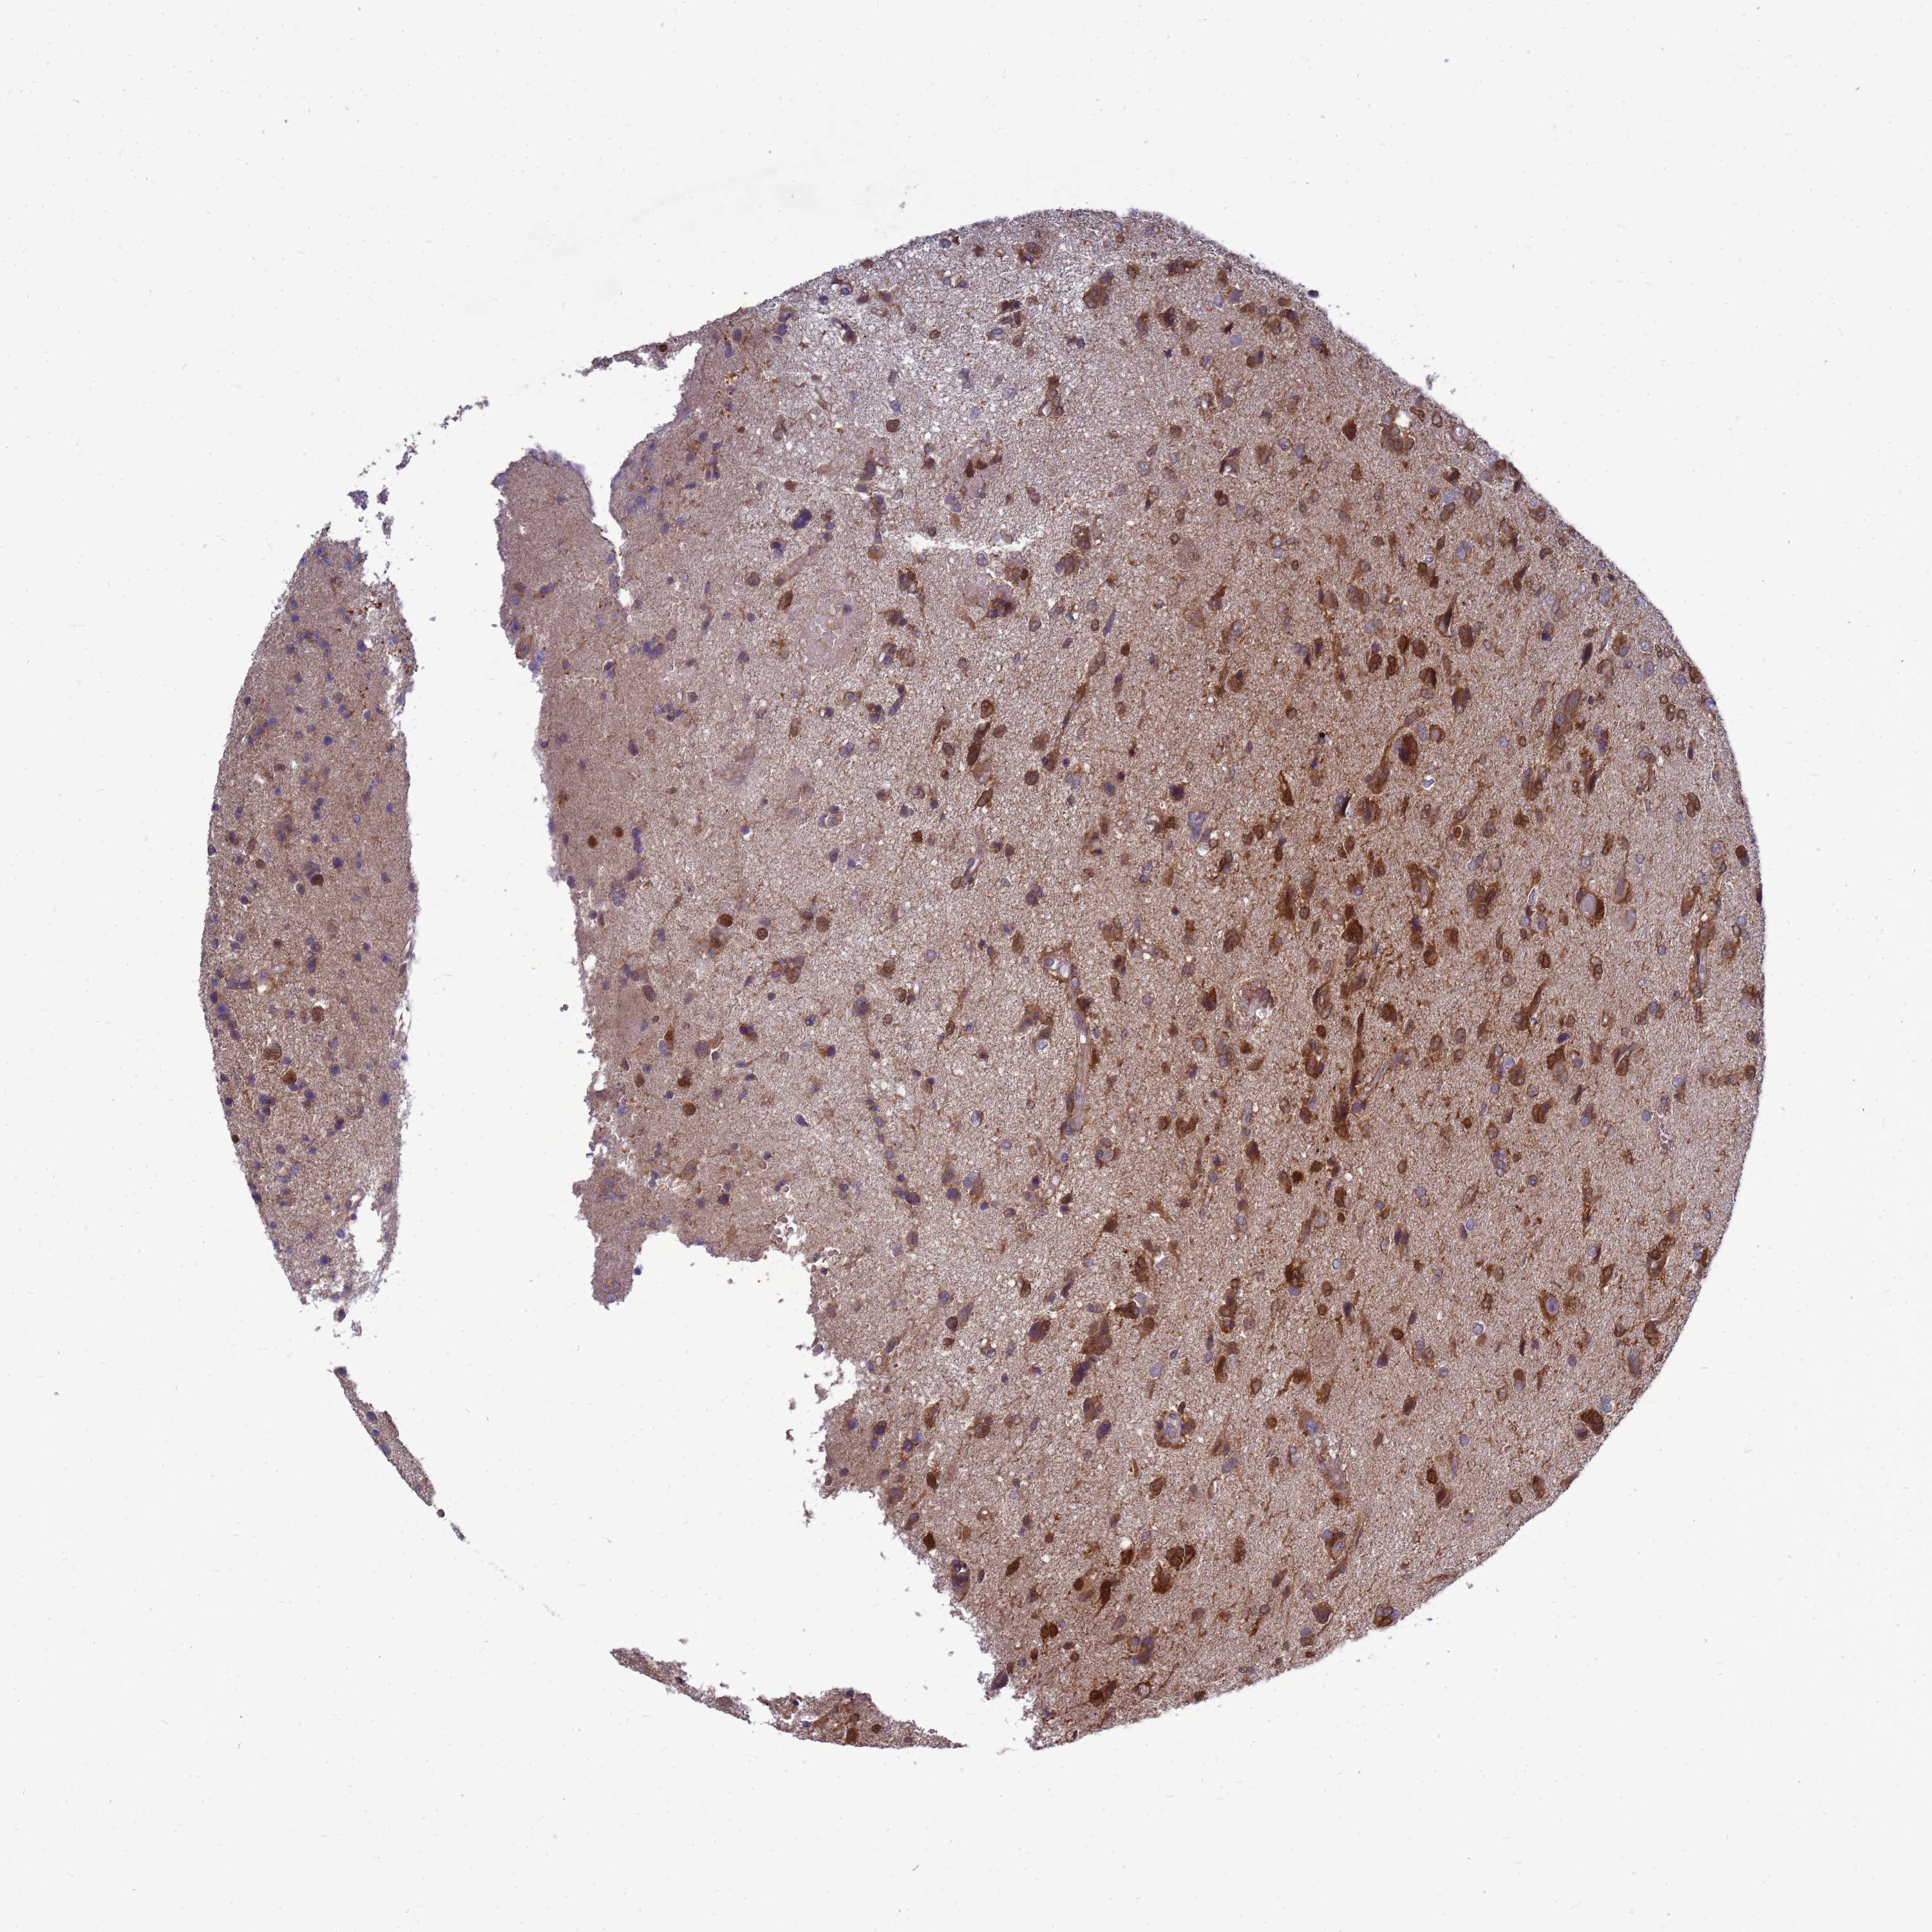

GLIOMA - Protein expressioni

A mouse-over function shows sample information and annotation data. Click on an image to view it in a full screen mode. Samples can be filtered based on level of antibody staining by selecting one or several of the following categories: high, medium, low and not detected. The assay and annotation is described here.

Note that samples used for immunohistochemistry by the Human Protein Atlas do not correspond to samples in the TCGA dataset.

Antibody stainingi

Antibody staining in the annotated cell types in the current human tissue is reported as not detected, low, medium, or high, based on conventional immunohistochemistry profiling in selected tissues. This score is based on the combination of the staining intensity and fraction of stained cells.

Each image is clickable and will lead to virtual microscopy that enables deeper exploration of all samples and also displays staining intensity scores, fraction scores and subcellular localization as well as patient and tissue information for each sample.

Antibody HPA045537

Staining

High

Medium

Low

Not detected

Intensity

Strong

Moderate

Weak

Negative

Quantity

>75%

75%-25%

<25%

None

Location

Nuclear

Cytoplasmic/membranous

Cytoplasmic/membranous,nuclear

Glioma, malignant, Low grade

Glioma, malignant, High grade

Glioblastoma, NOS